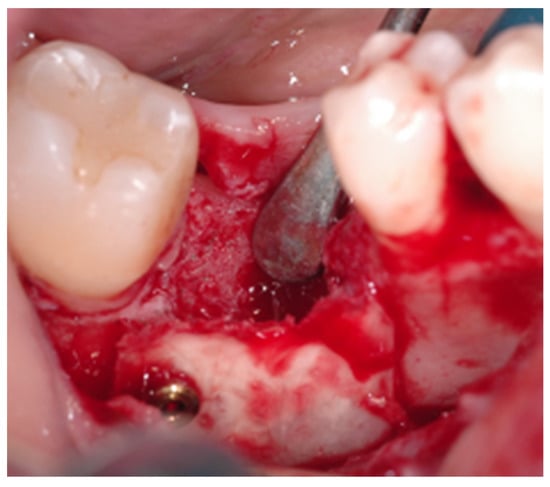

2.2. Surgical Procedure